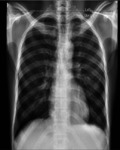

There are a few reported cases of bone metastasis from adenocarcinoma of the appendix and there is none from Africa. We report this rare case of a 30-year-old man who presented with low back pain following a trivial fall and who subsequently developed generalized peritonitis for which he underwent laparotomy. The histology of the appendix and the mesentery confirmed adenocarcinoma of the appendix with metastasis to the mesenteric lymph nodes while an MRI scan confirmed spine metastasis. Carcinoma of the appendix, should, therefore, be considered as a differential diagnosis in spine metastasis of unknown origin especially with coexisting abdominal symptoms.

Abstract Image